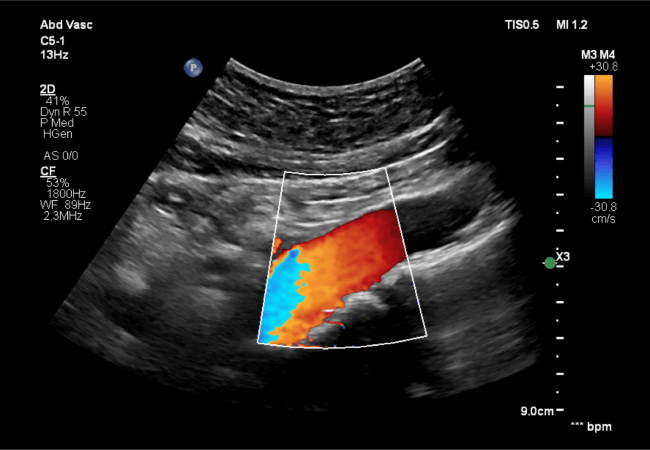

Abdominal Aorta Ultrasound

This test screens for aneurysms in the abdominal aorta, critical for early detection and management of this potentially life-threatening condition.

Aorta Ultrasound